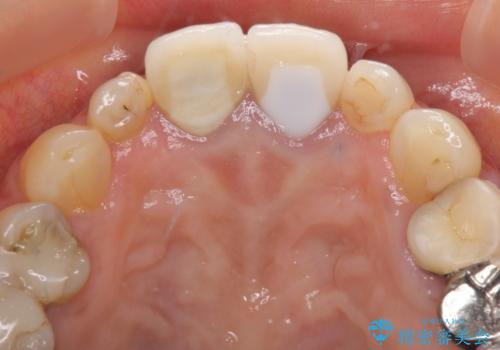

- 神経の抜いた歯が折れてしまい、痛みを感じて来院された患者様です。

折れてしまった歯は抜歯せざるを得ないため、抜歯と同時に仮歯を装着し、その後オールセラミックブリッジにて補綴することとしました。

折れた前歯を抜歯すると、歯肉が痩せてしまい、ブリッジの形態の審美性が失われることがあります。仮歯を調整することで審美回復が必要であるか判断しますが、今回は歯肉移植を行うことなく補綴治療を行いました。